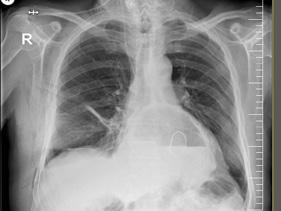

Figura 3. Stadializarea sindromului. IC=insuficiență cardiacă. FiA=fibrilație atrială. SCC=sindrom coronarian cronic. AVC=accident vascular cerebral. BAP=boală arterială periferică. Imagine preluată și tradusă de autori din documentul AHA1